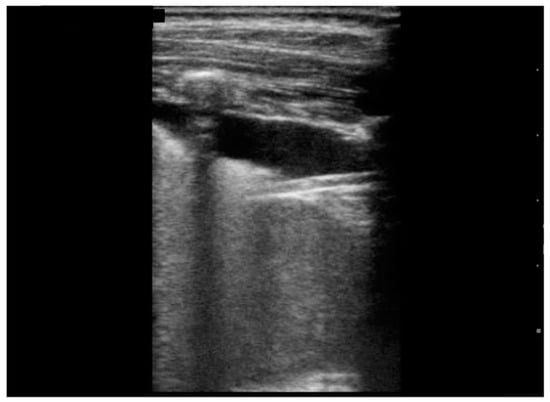

| Pleural effusion, n (%) | 9 (90) | |